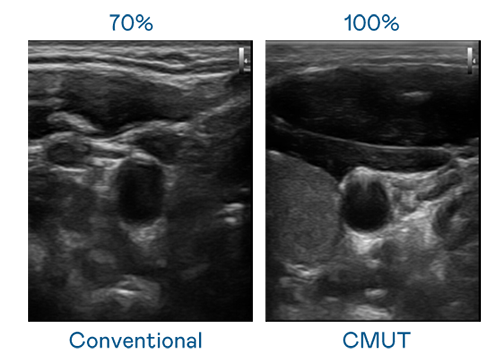

CMUT 技术是一种用电容式微机电元件来产生超音波讯号的技术。与传统 PZT 压电式技术相比,CMUT 频宽增加 30%,更宽频的超音波讯号让影像解析度大幅提升,是实现高影像品质医疗超音波扫描、促进精准医疗发展的关键技术。

大频宽带来超清晰影像

超音波影像的解析度高低,首先取决于探头能发出的讯号频宽。pg电子y92com CMUT 可提供高清晰的超音波讯号,提供高频宽、高灵敏度、影像纹理细节更高的超音波影像,协助医护人员缩短影像判读时间及利用精准的医疗影像进行诊断。